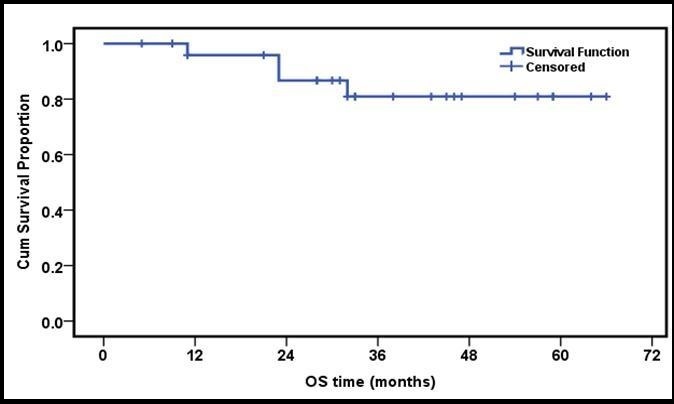

The 3 year estimated OS and EFS rates were 83.3% and 80.7% respectively (Figure 1 and Figure 2).

Figure 1.3 years OS of the whole group of patients

The 3 year estimated OS and EFS rates were 83.3% and 80.7% respectively, that was similar to what has been reported by other groups 28, 29, 30